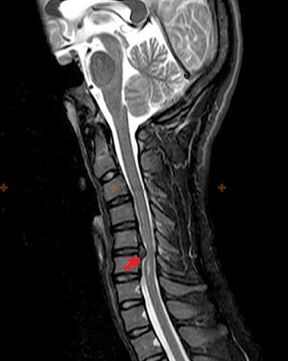

Osteokondroosi diagnoosimiseks kasutatakse järgmisi uurimismeetodeid: radiograafia (eelistatavalt funktsionaalsete testidega), MSCT ja MRI. Viimane uuring on kõige eelistatavam, kuna see võimaldab väga selgelt visualiseerida lülidevaheliste struktuuride seisundit.

Eespool kirjeldatud muutuste olemasolu, samuti MSCT ja MRI abil tuvastatud muutused lülidevahelise ketta struktuuris on usaldusväärsed märgid, mis kinnitavad osteokondroosi esinemist.